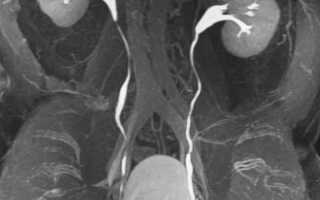

Нормальная картина

В норме почечная паренхима несколько плотнее печеночной, но значительно уступает по плотности костной ткани, которая на компьютерных томограммах имеет белый цвет. Плотность собирательных трубочек обычно сравнительно небольшая, и они на томограммах имеют темный цвет. При введении контрастного вещества плотность собирательных трубочек увеличивается и они приобретают светлый оттенок. Расположение почек оценивают относительно смежных образований. Размеры и форму почек определяют считыванием срезов между верхним и нижним полюсами и очерчиванием их контуров.

Отклонение от нормы

Объемное образование имеет плотность, отличную от плотности неизмененной паренхимы, и может изменять форму почки. Так, киста почки имеет вид гладкого тонкостенного образования с резко очерченными границами и плотностью, меньшей, чем у неизмененной паренхимы. Опухоли, например рак почки, обычно имеют менее четкие границы и неоднородные по плотности. При введении контрастного вещества солидные опухоли становятся плотнее, чем кисты, но их плотность не достигает плотности нормальной паренхимы. Опухоли с очагами кровоизлияний, обызвествления или некроза имеют большую плотность. Сосудистые опухоли после контрастирования визуализируются более четко. Опухоли надпочечников обычно имеют вид образований, отделенных от почки и окружающих органов забрюшинного пространства. С помощью КТ можно также диагностировать и другую патологию почек, включая обструкцию мочевых путей, мочекаменную болезнь, поликистозную болезнь, врожденные пороки развития, патологические скопления жидкости в паранефральном пространстве (гематома, лимфоцеле, абсцесс). После нефрэктомии КТ может выявить патологическое образование в почечном ложе, свидетельствующее о рецидиве опухоли.